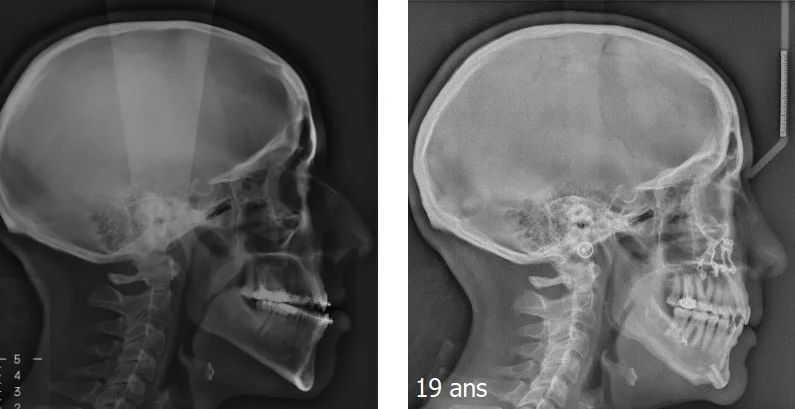

Chirurgie orthognathique

Classe III